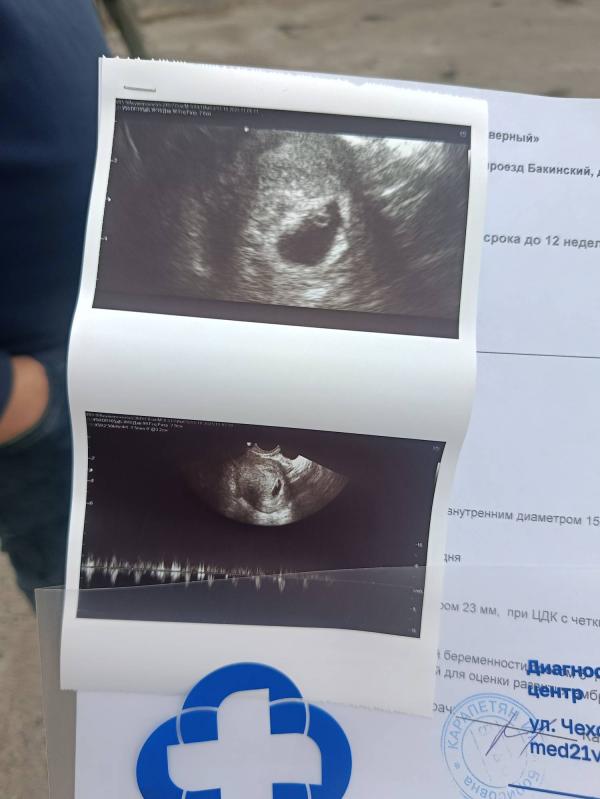

Сегодня я сходила на УЗИ. Срок моей беременности сейчас 6 недель и 3 дня. Сердечко малыша уже бьется, и сегодня я впервые его услышала. Это было так трогательно! Врач сказал, что все идет хорошо, и я очень рада этому. Теперь я с нетерпением жду следующего визита, чтобы снова увидеть своего кроху. Это такой волнительный период в моей жизни, и я наслаждаюсь каждой его минутой❤❤❤💘